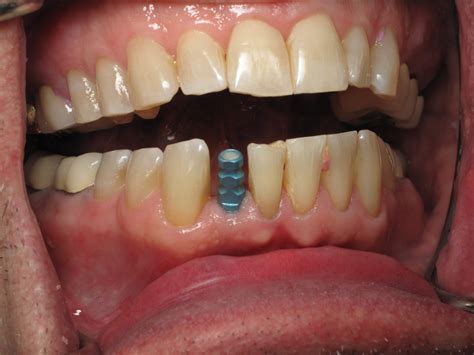

Implant Placement Surgical insertion of the titanium post into the jawbone.

Osseointegration A healing period of 3–6 months where the bone fuses to the implant.

Another common concern is the "temporary" phase. Because the front area is visible, dentists often provide a temporary prosthetic (such as a flipper or a temporary crown) immediately after the surgery. This ensures that you do not have to walk around with a visible gap while the underlying bone and gum tissue heal.